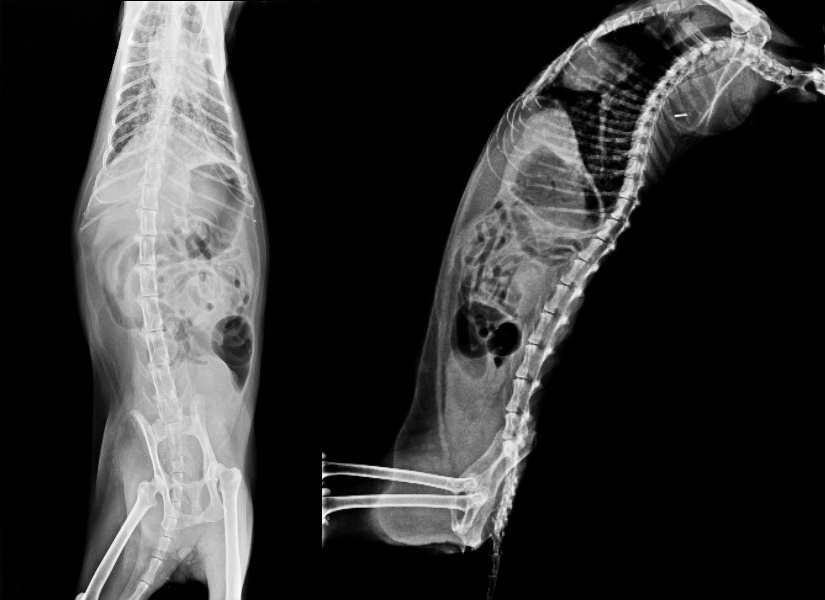

但近月又開始食慾不振……上週她在我面前遛達,驚訝發現她變得好瘦,兩隻後腿左右極不對稱,隔日送醫後,X光檢查發現肺部有陰影、鼠蹊部與右後腿已佈滿小腫塊,疑似先前乳腺癌復發與腫脹轉移、擴散。

這次就醫Milka 已不吃不喝,眼神不如以往,我知道她時間已到,今天探望她,還可以撫摸她,只希望在最後的日子裡,她的身體不需承受太大苦楚,晚間十點半接獲醫師電話,Milka完成一生功課畢業了...

醫療費用共25830元

火化費用5000元

共計30830元